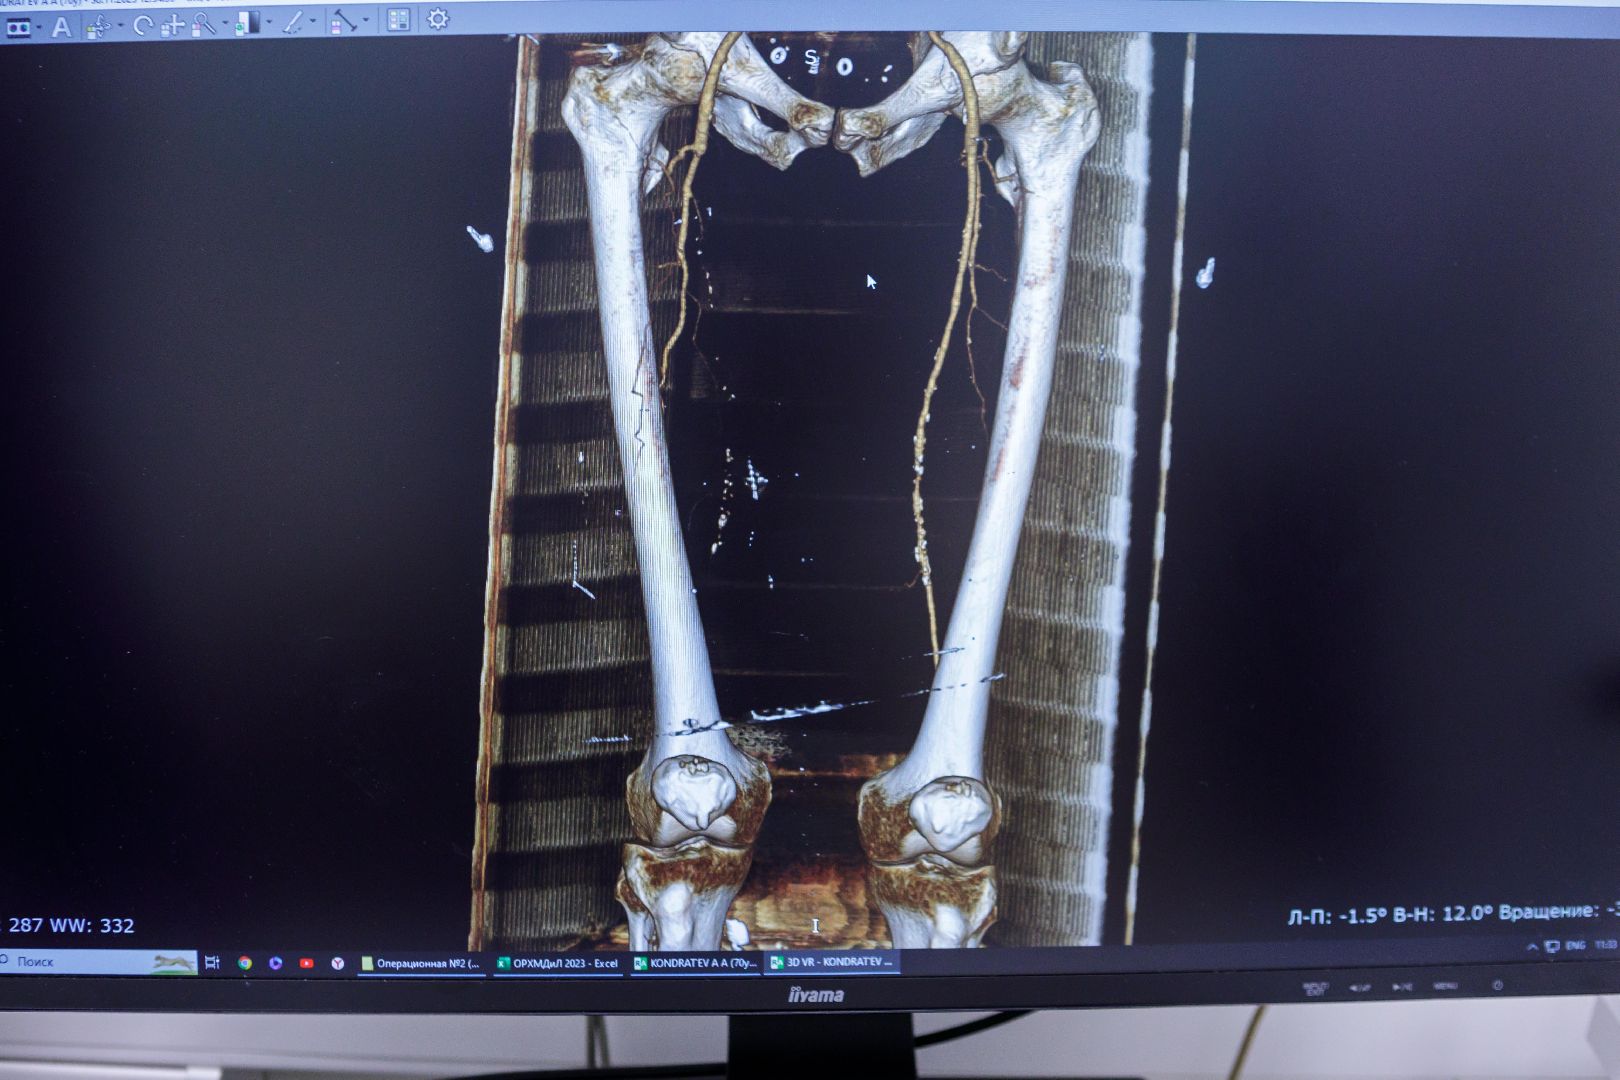

«Золотым стандартом исследования при поражении сосудов является КТ-ангиография, которая проводится также на базе нашей больницы. Это когда в вену пациента вводится контрастное вещество, которое прокрашивает все сосуды, и с помощью специальной программы мы можем измерить диаметр поврежденного сосуда, определить длину пораженного участка. По итогам в результате консилиума с рентген-хирургами разрабатываем план операции», — рассказывает заведующий отделением сосудистой хирургии Агита Разгоев.